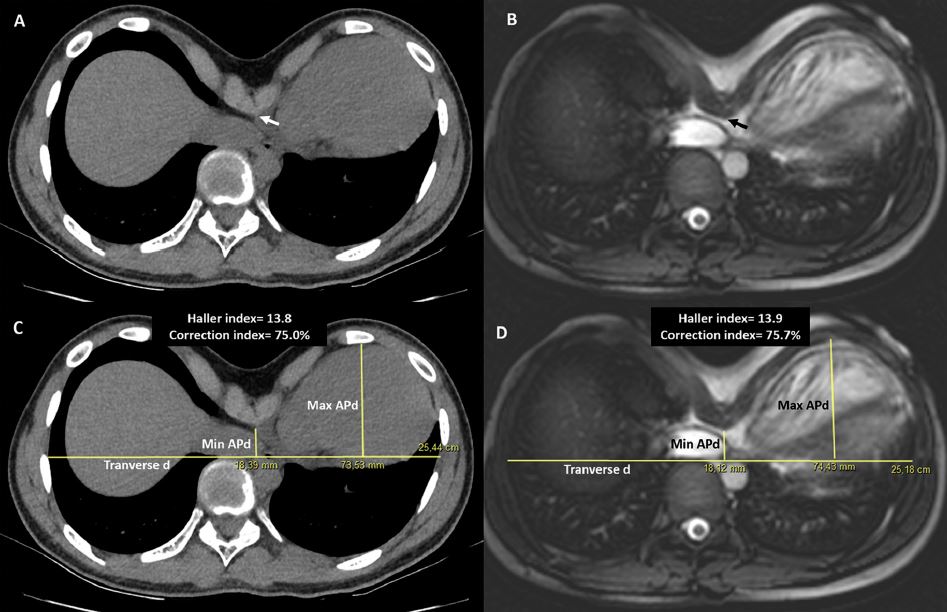

Métodos: se incluyeron pacientes consecutivos con TEP remitidos para ser sometidos a TC de tórax y RMC para establecer candidatura y / o definir estrategias de tratamiento. Tanto la TC como la RMC se realizaron a la espiración completa. En ambos modalidades, el índice de Haller (HI) y el índice de corrección (IC) fueron calculados por dos observadores independientes. En CMR, solo se utilizaron imágenes scout. La concordancia se evaluó mediante coeficientes de correlación intraclase (CCI).

Resultados: Cincuenta pacientes comprendieron la población de estudio (mediana de edad 19,0 años) y se sometieron a TC de tórax y RMC. dentro del mismo mes. La evaluación por RMC de los índices de malformación torácica fue reproducible, con una muy buena acuerdo interobservador para HI [ICC 0,93 (0,88-0,96), p <0,0001] e IC [ICC 0,91 (0,83-0,95), p <0,0001]. La RMC también tuvo una muy buena concordancia con la TC de tórax para HI [ICC 0.90 (0.82-0.94), p <0.0001] y mediciones de IC [ICC 0,93 (IC del 95%: 0,88-0,96), p <0,0001].

Conclusiones: Demostramos una excelente concordancia entre la TC de tórax y la RMC estándar para la evaluación de malformaciones de la pared torácica, lo que potencialmente permite la evaluación preoperatoria de la gravedad de la EP y la afectación cardíaca con una única herramienta de diagnóstico.